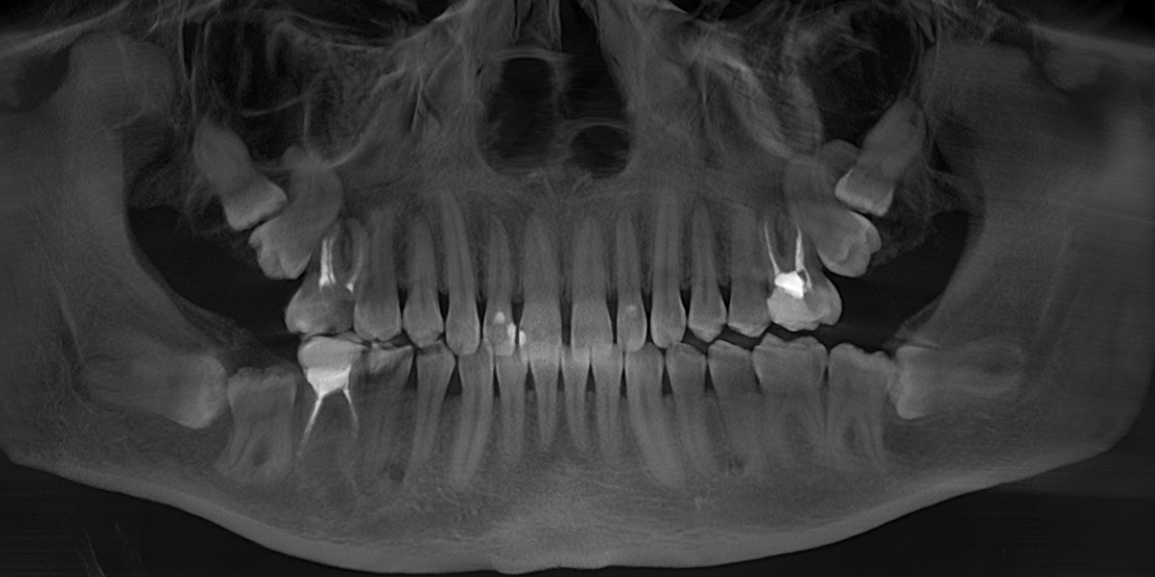

Когда же вы уже поймете, что для удаления подобных зубов:

требуется 20 минут, а никак не трехчасовой наркоз и трое суток в стационаре. (подобный случай я описывал подробнее в этой статье)

А для таких:

Чуть меньше часа (отдельно верх, отдельно низ):

В данном случае я очень долго и подробно рассказывал молодому человеку обо всех возможных осложнениях, особенностях восстановления и дальнейшем протезировании. Более того, я планирую написать полноценную статью по этому клиническому случаю, когда у пациента будут стоять имлантаты.